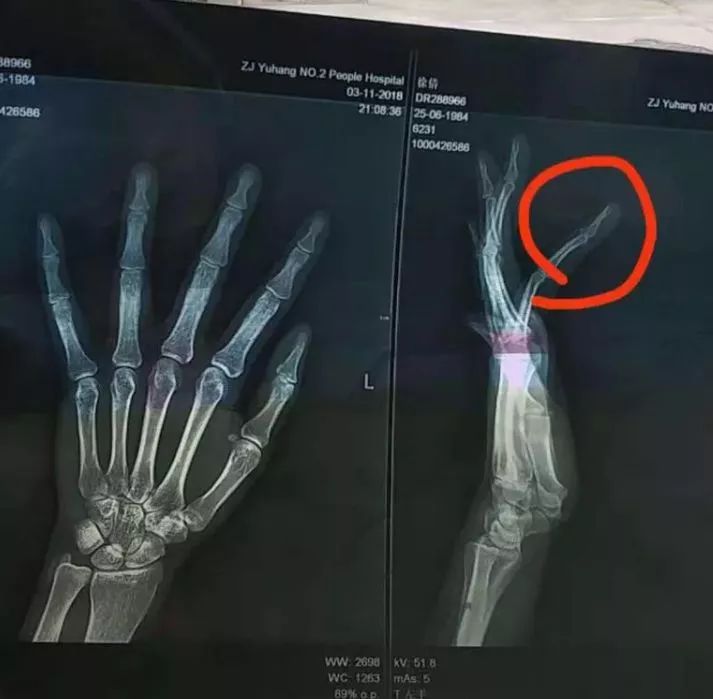

手骨裂x光片

手骨裂x光片,轻微骨裂拍片子图片

右手第五掌骨撕脱性骨折,麻烦大家帮忙看下x光片,谢谢